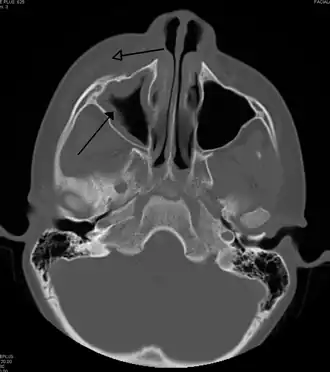

| Periorbital cellulitis caused by a dental infection (also causing maxillary sinusitis) | |

Periorbital cellulitis, or preseptal cellulitis, is an inflammation and infection of the eyelid and portions of skin around the eye anterior to the orbital septum.[1] It may be caused by breaks in the skin around the eye, and subsequent spread to the eyelid; infection of the sinuses around the nose (sinusitis); or from spread of an infection elsewhere through the blood.

Periorbital cellulitis must be differentiated from orbital cellulitis, which is an emergency and requires intravenous (IV) antibiotics. In contrast to orbital cellulitis, patients with periorbital cellulitis do not have bulging of the eye (proptosis), limited eye movement (ophthalmoplegia), pain on eye movement, or loss of vision. If any of these features is present, one must assume that the patient has orbital cellulitis and begin treatment with IV antibiotics. CT scan may be done to delineate the extension of the infection.

Tests include blood work (CBC) to rule out infectious cause. Also perform a CT scan, x ray of the anterior skull to view the sinuses, MRI scan and finally a soft tissue ultrasound of the orbital region.